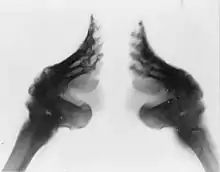

At the beginning of the binding, many of the foot bones would remain broken, often for years. However, as the girl grew older, the bones would begin to heal. Even after the foot bones had healed, they were prone to rebreaking repeatedly, especially when the girl was in her teenage years and her feet were still soft. Bones in the girls' feet would often be deliberately broken again to further change the size or shape of the feet. This was especially the case with the girl's toes, which were broken multiple times as small toes were especially desirable.[90] Older women were more likely to break hips and other bones in falls, since they could not balance properly on their feet, and were less able to rise to their feet from a sitting position.[91] Other issues that may have arisen from footbinding included paralysis and muscular atrophy.[86] By the turn of the century, footbinding had been exposed in photographs, X-rays and detailed textual descriptions. These scientific investigations detailed how footbinding deformed the leg, covered the skin with cracks and sores and altered the posture.[92]